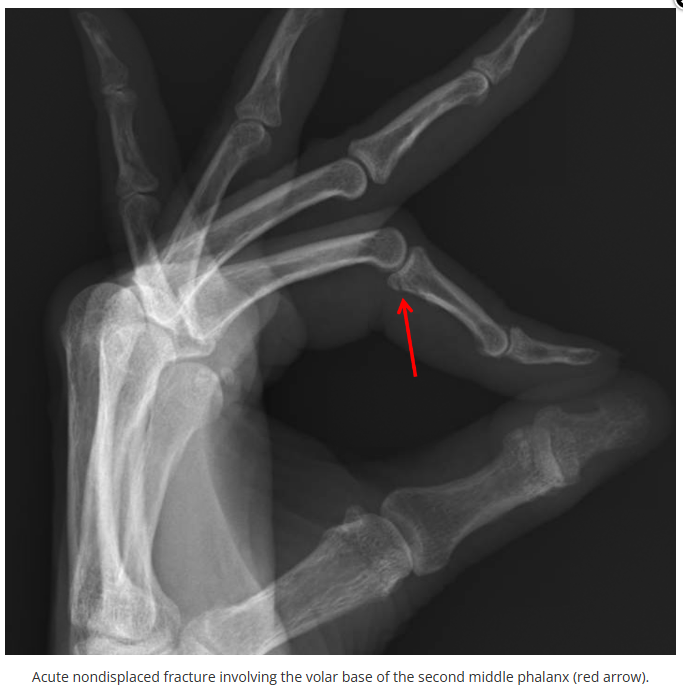

这些腕与手的骨折X线片如果没有标注箭头,你还能识别出来吗?

X线读片是骨科医生的基本功。

今天是腕部与手的X线片。所有X线片都

带有标注和说明

,可以选择长按图片,

自动翻译相关说明

。